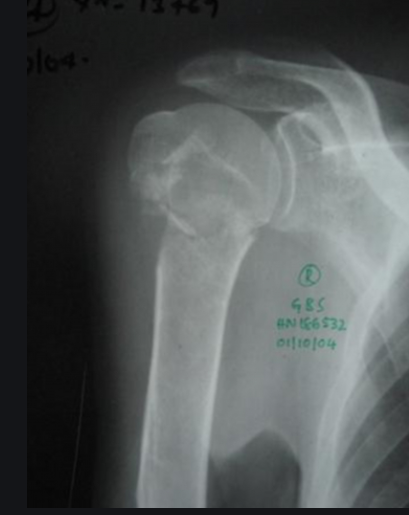

Gãy cổ phẫu thuật xương cánh tay là gãy xương thường gặp, chiếm 60 % gãy xương đầu trên xương cánh tay, hay gặp ở người lớn tuổi , nữ gặp nhiều hơn nam do tình trạng loãng xương.

TRIỆU CHỨNG

- Bệnh nhân sau ngã đập vai xuất hiện sưng, đau , bầm tím vùng vai

- Biến dạng vai nếu gãy có di lệch xương, mất vận động hoặc hạn chế vận động vai, cánh tay

- Ấn có điểm đau chói đầu trên cánh tay, có thể có cử động bất thường , tiếng lạo xạo xương